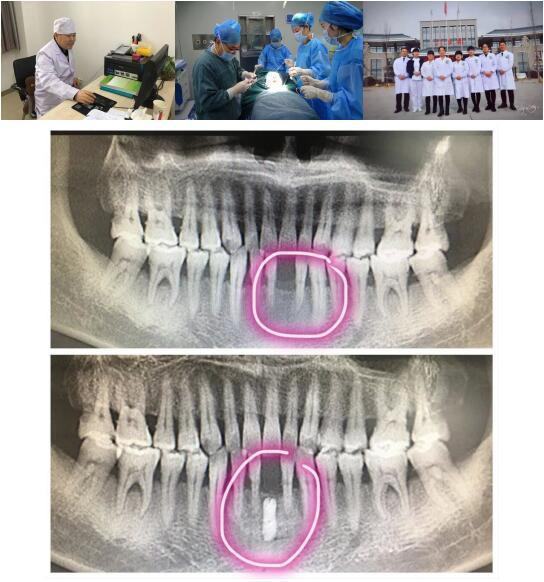

探花av 高陵院区口腔科成功开展一例GBR引导骨再生技术种植牙